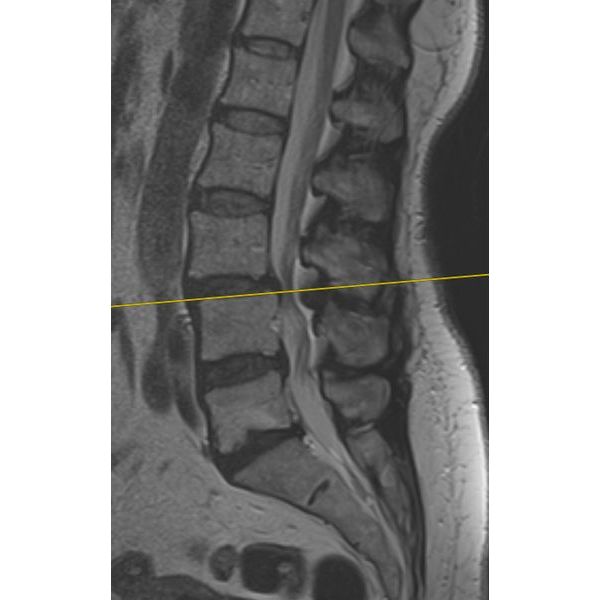

По результатам функционального рентгенологического исследования поясничного отдела позвоночника, у пациентки отмечалась нестабильность на уровне сегмента L3–L4: при наклоне туловища позвонок L3 смещался вперёд на 3 мм, угол раскрытия составил 10°.

МРТ поясничного отдела позвоночника подтвердило диагноз.

Остеохондроз поясничного отдела позвоночника, дегенеративный спондилолистез (смещение) L3, спондилоартроз 3–4-й (тяжёлой) степени, функциональная несостоятельность позвоночника, нестабильность сегмента и дегенеративный стеноз позвоночного канала на уровне L3–L4 (по классификации Schizas — степень С), нейрогенная перемежающаяся хромота, люмбалгия.